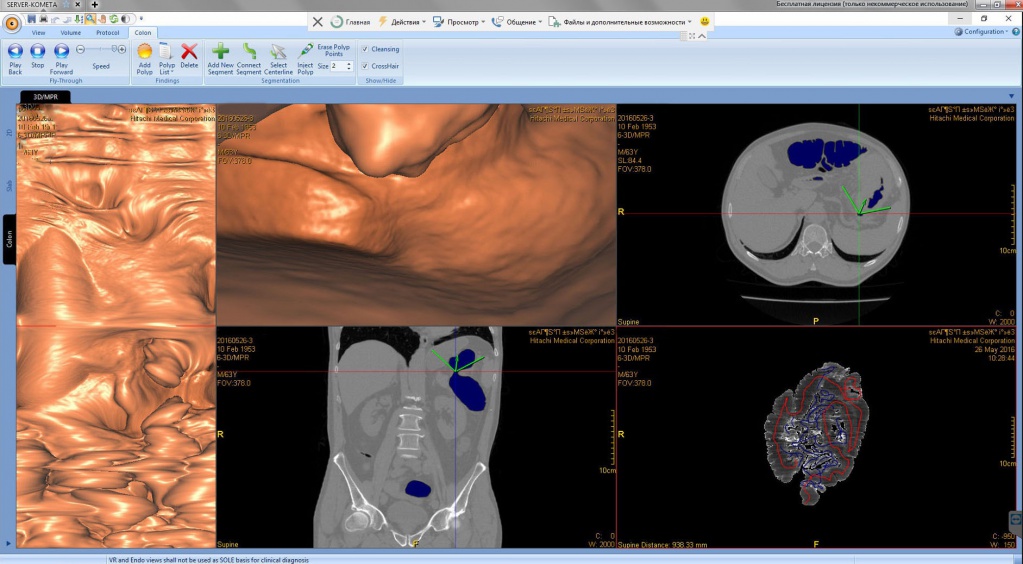

Рак ободочной кишки в зоне селезёночного угла с прорастанием опухоли в переднюю стенку желудка

Патология с точки зрения диагностики так и клиники интересна тем, что диагностировать удалось в полном объёме только на КТ, при проведении виртуальной колоноскопии. 3D реконструкция и в этом случае, как нельзя кстати. Пациент удачно прооперирован, с восстановлением физиологии пищеварительной трубки с относительно благоприятным клиническим исходом. Через год после комбинированного лечения отдалённых метастазов не выявлено.

Компания «Комета» разработала полный комплект программных инструментов, которые в автоматическом режиме выстраивают путь прохождения кишечника с автоматическим виртуальным 3D-эндоскопом, что во многом убыстряет проведение оценки пищеварительной трубки изнутри врачом рентгенологом, а также сохраняется возможность увидеть кишечник заполненный газом в 3D (форма, размеры, положение, дефекты). Имеется функция разреза кишки и просмотра органа в развернутом виде на всем протяжении. Данный функционал устанавливается в комплекс 3Di-PACS регионально, что имеет безусловное преимущество перед конкурентами, как по использованию, так и по себестоимости.